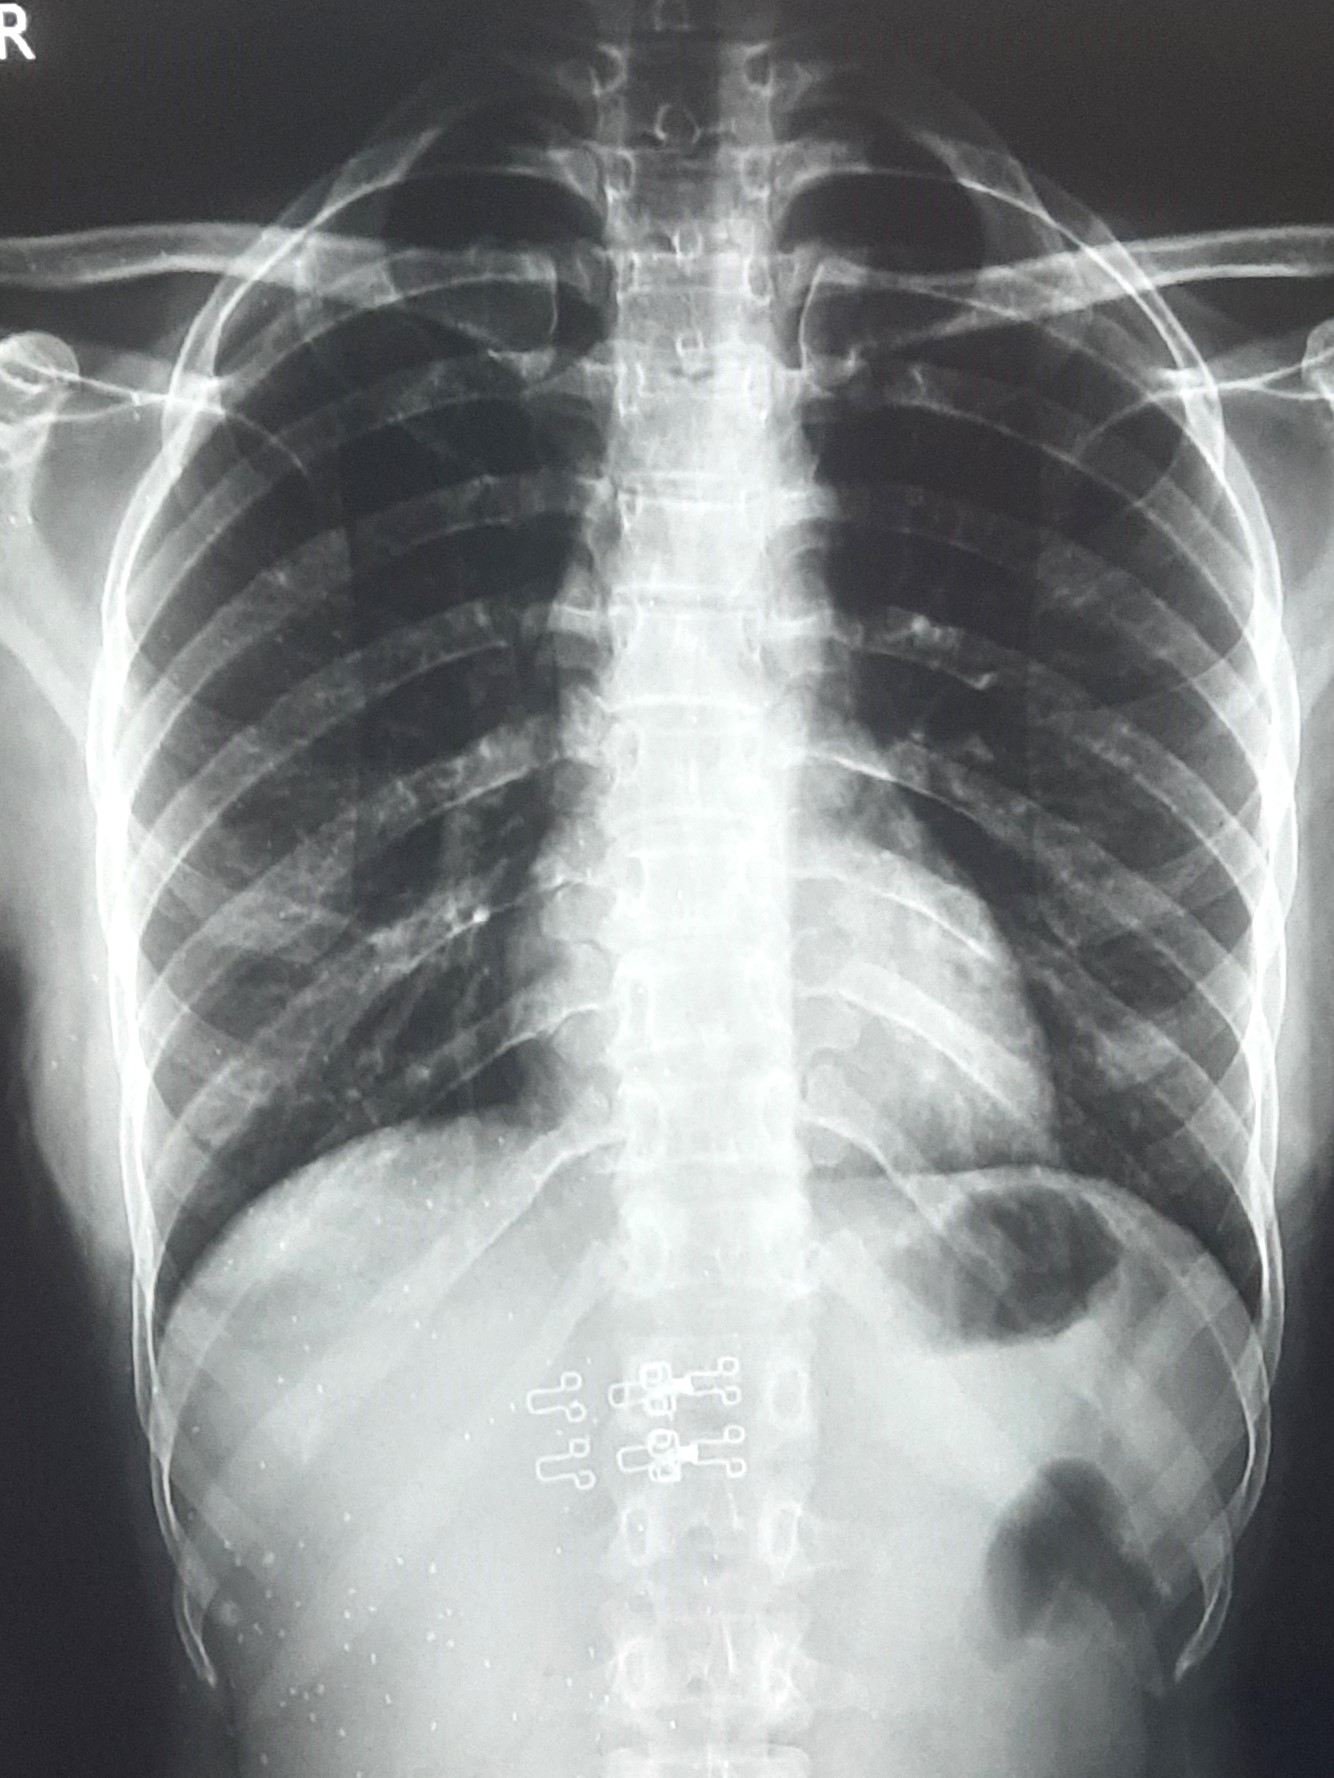

| IGGMC, Nagpur | 29-4207 | IGGMC, Nagpur | Nisha Suryawanshi | H/O TB In 2022 Completed 6 Month |

| Chest X-Ray Image |